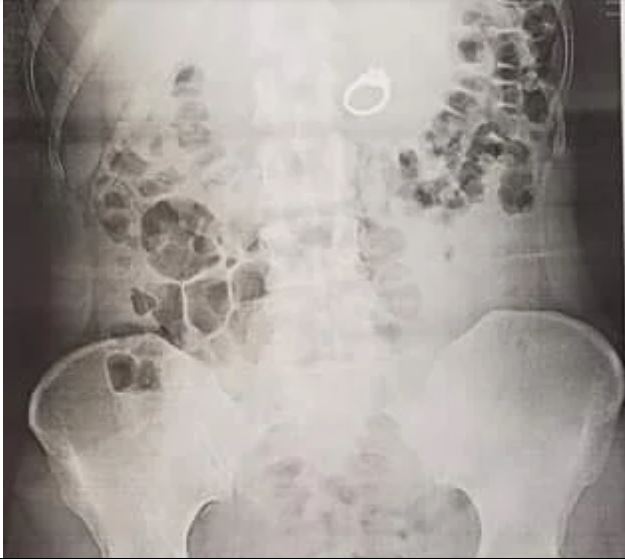

I went to urgent care where I struggled to explain why I was there, because I was laughing/crying so hard. The doctor ordered an Xray and seemed pretty shocked when she walked back in with a second doctor and showed me that sure enough, my ring was right there in my stomach!